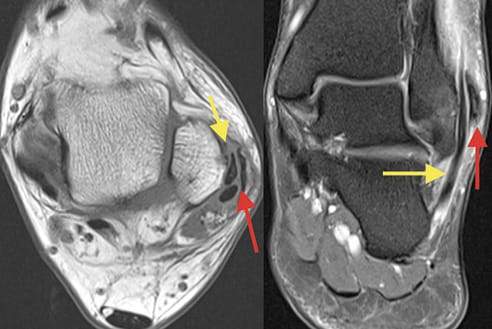

Échographie L'échographie musculo-squelettique du membre inférieur : sémiologie et applications de l'échographie en présence d'une aponévropathie plantaire